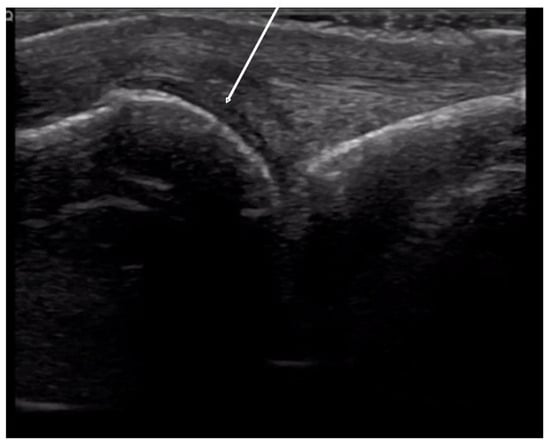

2.1.2. Inflammatory Arthritis

2.1.3. Acro-Osteolysis

4.1. Evaluation of the Fingers

4.1.1. Dorsal Aspect